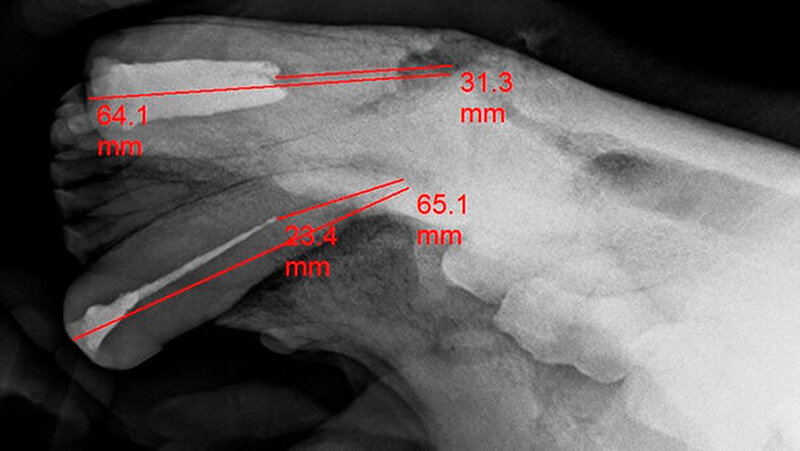

Drittens: Wurzelkanalbehandlungen an den Fangzähnen, den Dentes Canini, bedeuten aufgrund der extremen Länge von 70 bis 80 Millimetern bei großem Kanallumen eine enorme Herausforderung. Sie erfordern einen hohen Aufwand bezüglich der Darstellung und des „Flarings“ des gekrümmten Kanallumens mit Lindemannfräsen (60 Millimeter) und langen Wurzelkanalfeilen (75 bis 90 Millimeter), um die notwendige Arbeitslänge zu erreichen. Die elektrometrische Längenbestimmung funktioniert bei diesen Dimensionen nicht wirklich präzise, so dass man ohne eine Röntgen-Mess-Aufnahme zu einer fehlerhaften Längenabstimmung kommt.